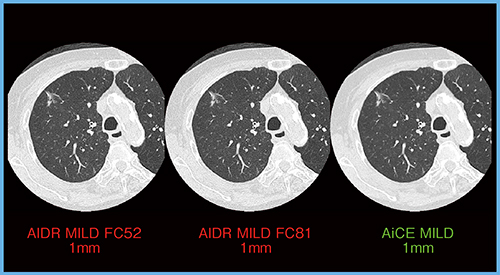

肺がんのGGO(すりガラス状陰影)の症例であるが,当院では通常,AIDRのFC52とFC81の関数を使い分けて再構成している。AiCEのLungパラメータで再構成した画像と比較すると,AiCEではドット抜けのようなノイズが低減され,クリアになっていることがわかる(図7)。

図7 肺がん(GGO)

(撮影条件:80Helical scan,0.35s/rot,120kVp,CTDIvol 5.3mGy,DLP 188.7mGy・cm)